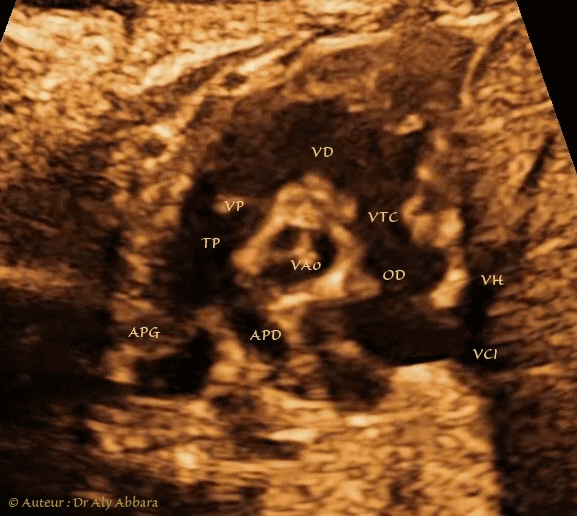

Image échographique animée montrant les éléments anatomiques composant le cœur droit :

La veine cave inférieure (VCI) et la veine hépatique commune (VH) qui se connectent à l’oreillette droite (OD) ; la valve tricuspide VTC (ou valve atrio-ventriculaire droite) ; le ventricule droit (VD) ; la voie d'éjection du ventricule droit ; la valve pulmonaire (VP) et ensuite le tronc pulmonaire (TP) qui se divise en deux artères : l'artère pulmonaire droite (APD) et l'artère pulmonaire gauche (APG).

Il s'agit d'une coupe axiale sur l'aorte ascendante passant au niveau de la valve aortique (VAo) que on peut identifier par ses trois feuillets.

Cette " Coupe de petit axe " est utilisée pour mesurer le diamètre du tronc pulmonaire ; elle permet également la mise en évidence des CIV du septum conal qui sont appelées les CIV conoventriculaires ; infundibulaires ; sous artérielles ou subpulmonaires.

Foetus âgé de 36 SA.